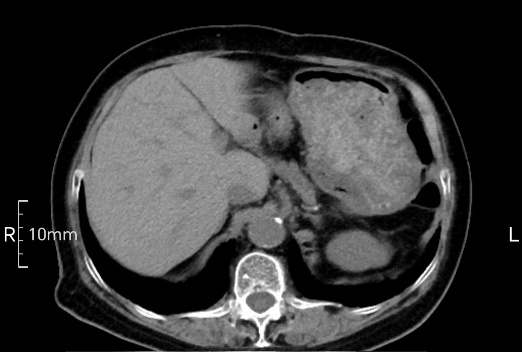

看看下面三幅便知遵醫(yī)囑的重要性。

沒(méi)禁食,胃內(nèi)全是食物,導(dǎo)致胃壁顯示不清。